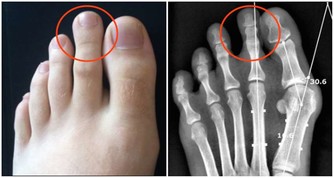

今年6月26日早上, 剛剛起床的蘇先生被鄰居急促地叫喊, 「快去看看, 正躺在大街上的那個小孩是不是你兒子。 」匆忙趕到現場後, 蘇先生看到兒子正仰面躺在大街邊, 手、腳嚴重腫脹, 人事不省。

他迅速撥打120, 將蘇煜拉到了當地一家醫院,經檢查醫生拿著拍的片子說,「這治不了,肺都爛了。」蘇先生便帶著兒子趕到了省胸科醫院。 網咖人員聚集、空間密閉,易感染結核病菌 在省胸科醫院內,醫生通過檢查確診,蘇煜患的是嚴重肺結核,大部分肺已經被結核菌侵蝕掉。同時,他還伴有胸腔積水、上消化道出血。 經過一系列治療後,蘇煜逐漸甦醒過來。面對父母,他說得最多是「後悔」。 「前一段時間,剛接診過一個病人,也是20歲左右的小夥子,因為長期泡網吧,結果感染上了結核性腦膜炎,到醫院不到兩天就死了。」省胸科醫院一位醫生說。 「集聚的人群,密閉的空間,很容易感染結核病菌。」這位醫生說,上網容易導致疲勞、自身免疫系統功能下降,再加上網咖的人員流動性大,空氣環境不好,一旦有一個傳染源,網吧裡的其他人很容易感染上。 網吧的空氣質量到底有多差?河南電視台《民生大參考》通過專用的雷射粉塵儀,實地檢測了一下當地市區部分網咖的空氣品質,結果讓人震驚!有網吧的pm2.5濃度最高的達到了2.1毫克每立方米,也就是2100微克每立方米!!